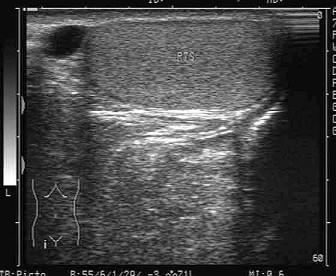

问题 某患者右侧阴囊根部可触及小包块,超声声像图如下,最可能的诊断为?(?)

选项 A.精索鞘膜积液 B.睾丸鞘膜积液 C.附睾囊肿 D.睾丸肿瘤 E.附睾血肿

答案 C